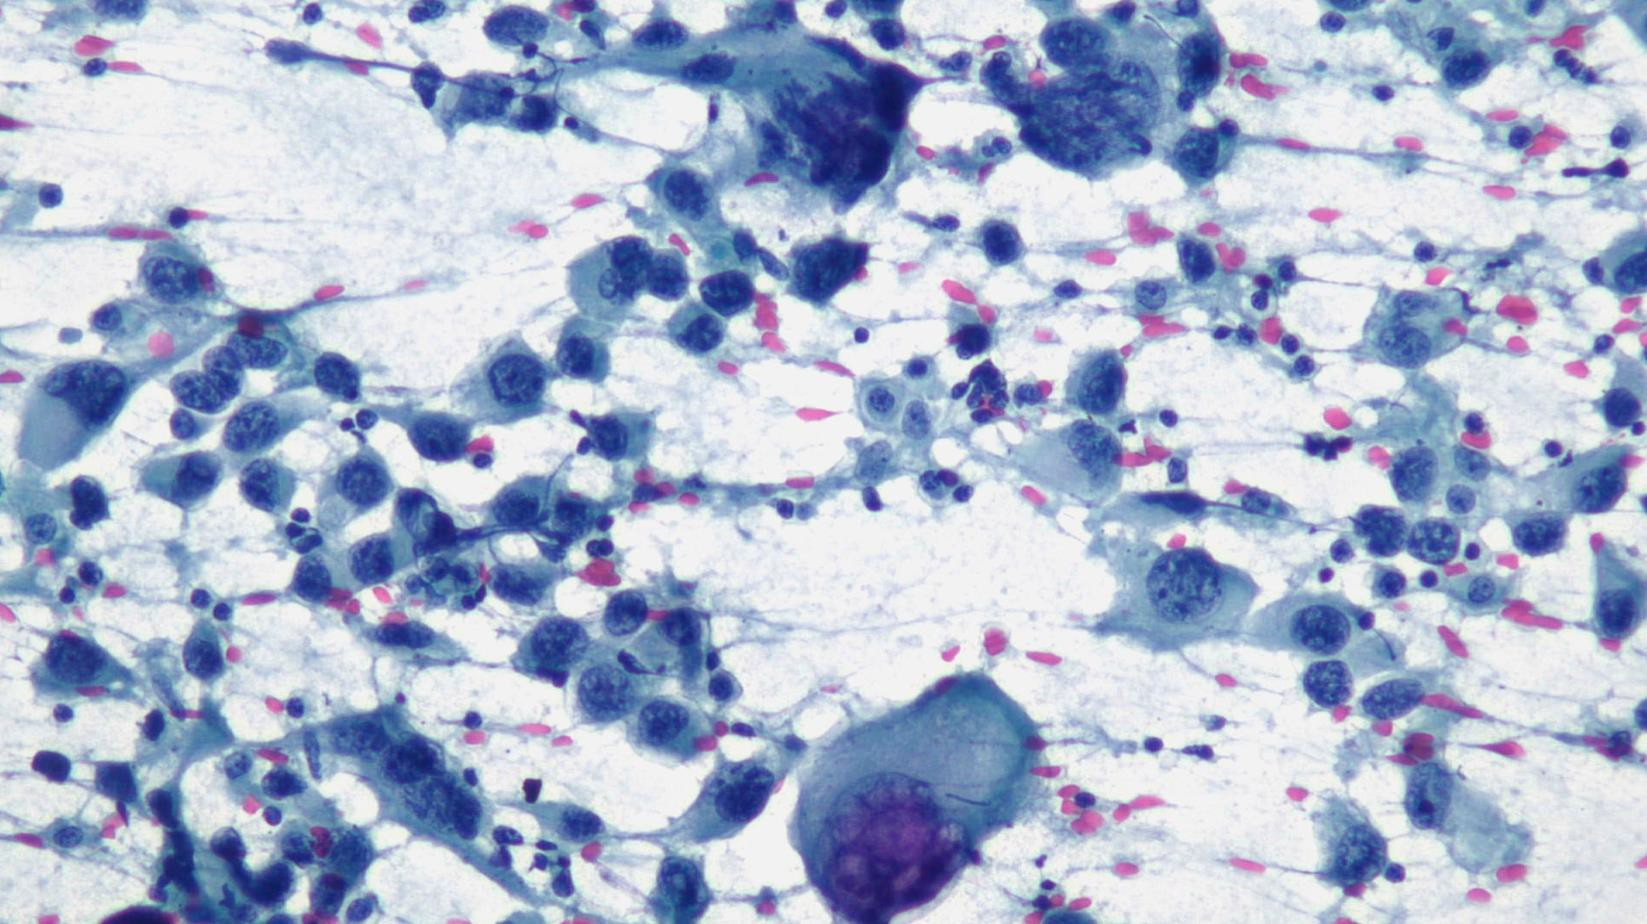

In the webinar “With good material, cytology is easy” Univ. Doz. Dr. Rickard Weger will discuss the importance of specimen quality for reliable cytological diagnosis. Using practical examples, he will show how good-quality material makes evaluation easier and improves diagnostic accuracy.

Schwerpunkt: Fine needle aspiration cytology (FNAC)/Feinnadelaspirationszytologie (FNAC)